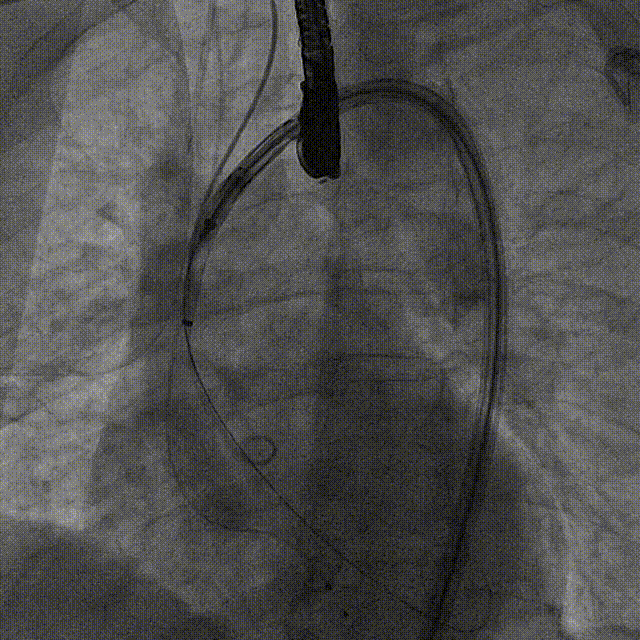

瓣膜对齐MARK

瓣膜调弯解离

瓣膜锚定键体位确认

瓣膜入窦

左窦确认